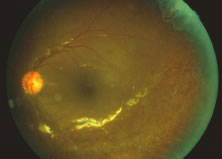

Both herpes simplex virus type 1 and herpes simplex virus type 2 (HSV-1, HSV-2) may cause ARN.20–22 In a single report, CMV particles were identified in and cultured from the retina of an enucleated eye of a nonimmunosuppressed patient suffering from bilateral ARN.23 VZV has been reported most frequently as the viral etiologic agent of ARN.2,3,24–27 We have demonstrated herpesvirus family viral particles in endoretinal biopsy specimens taken from patients in the active stage of the disease who showed an enormous viral load (Fig. 4). These studies, combined with the failure of many enucleated eyes with ARN to demonstrate evidence of viral particles, indicate that the virus is present only in the active stages of the disease and that a gliotic retina will not demonstrate the etiologic agent.28

A variable number of eyes, up to 75%, develop retinal detachments (Fig. 5). Prophylactic laser for demarcating the areas of active retinitis from normal retina has been advocated to create chorioretinal adhesions that prevent retinal detachments around sites of retinal break formation (which usually occur at the zone between affected and healthy retina). Han and associates43 reported five cases treated with prophylactic laserpexy in addition to antiviral, steroid, and antiplatelet therapy. After 15 months of follow-up, no retinal detachments were noted. Sternberg and coworkers44 described a 75% decrease in the rate of retinal detachment using prophylactic photocoagulation. Some have advocated the creation of a “new ora serrata” by applying confluent rows of laser burns posterior to the areas of retinitis. However, if traction forces from vitreous organization, epiretinal membrane (ERM) formation, or proliferative vitreoretinopathy develop as they commonly do, the contractile forces will be able to overcome any increased chorioretinal adhesion created by the laserpexy. However, McDonald and associates45 reported failure of prophylactic peripheral laserpexy to prevent retinal detachment in ARN patients. In addition, many cases of ARN result in a severe vitritis, limiting the view for a planned laserpexy (Fig. 6). Therefore, vitrectomy with endolaser and concomitant encircling of the eye with a scleral buckle to reduce traction may be required in some patients.46,47 Decisions relating to the need for scleral buckling to support retinal breaks and the use of silicone oil or long-acting gases to repair retinal detachments should be made by an experienced vitreoretinal surgeon.40,48 Selection of cases to undergo operation should be made with consideration given to optic nerve function, visual potential, and medical control of retinitis.